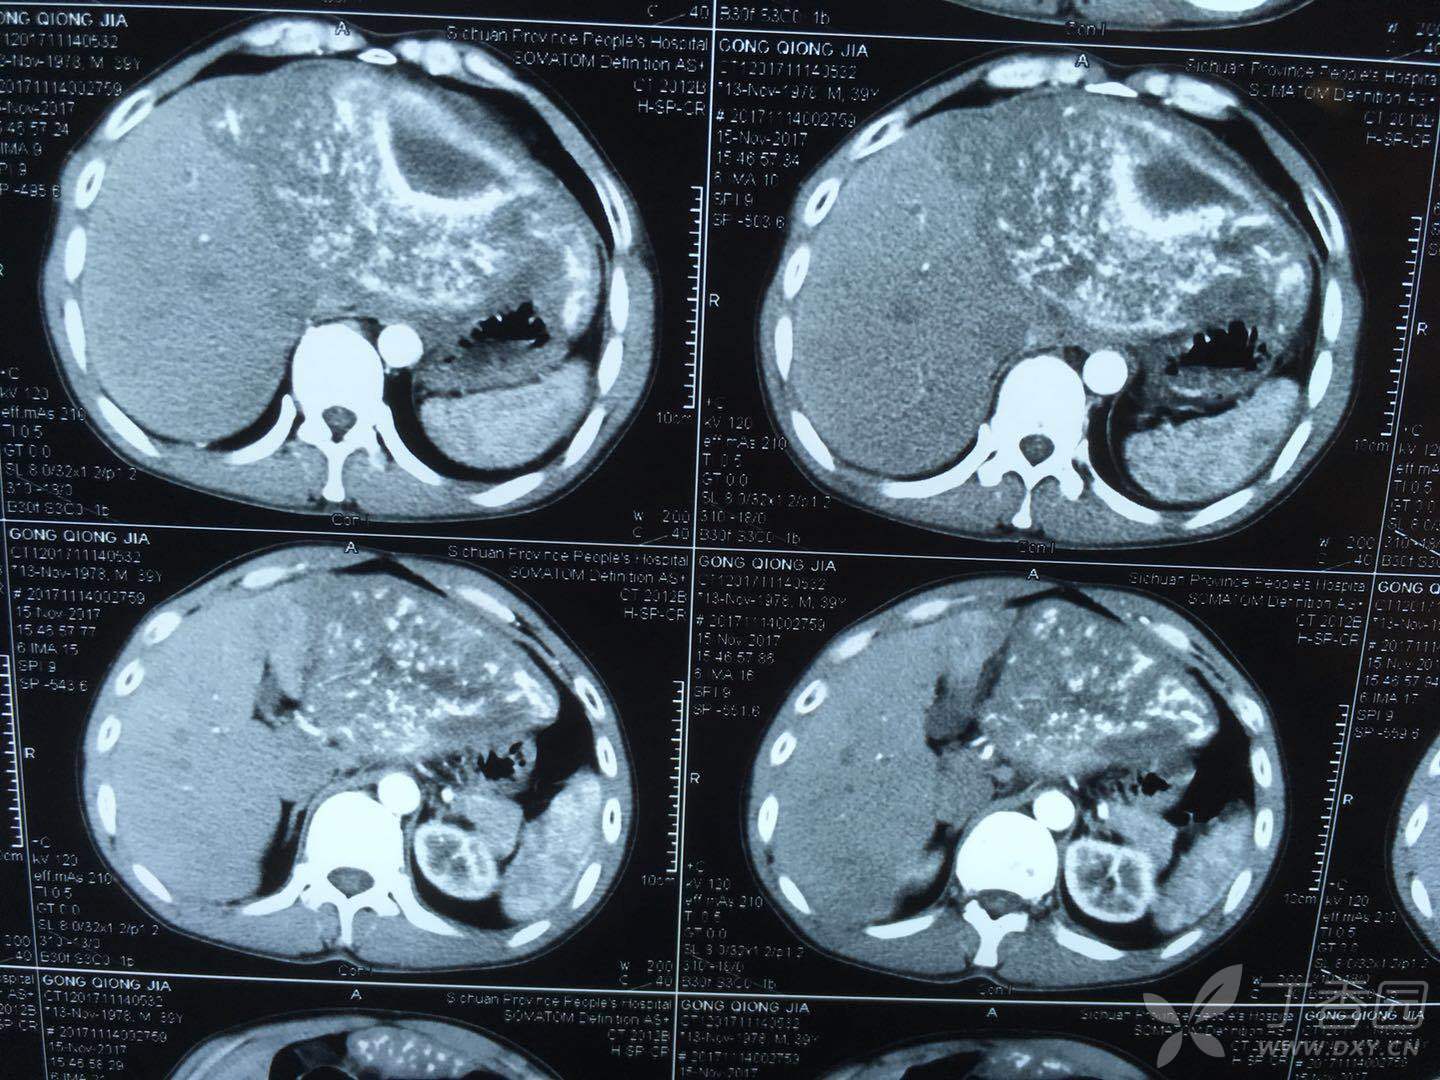

左肝巨大包虫一例 - 普通外科讨论版 -丁香园论坛

图片尺寸1440x1080